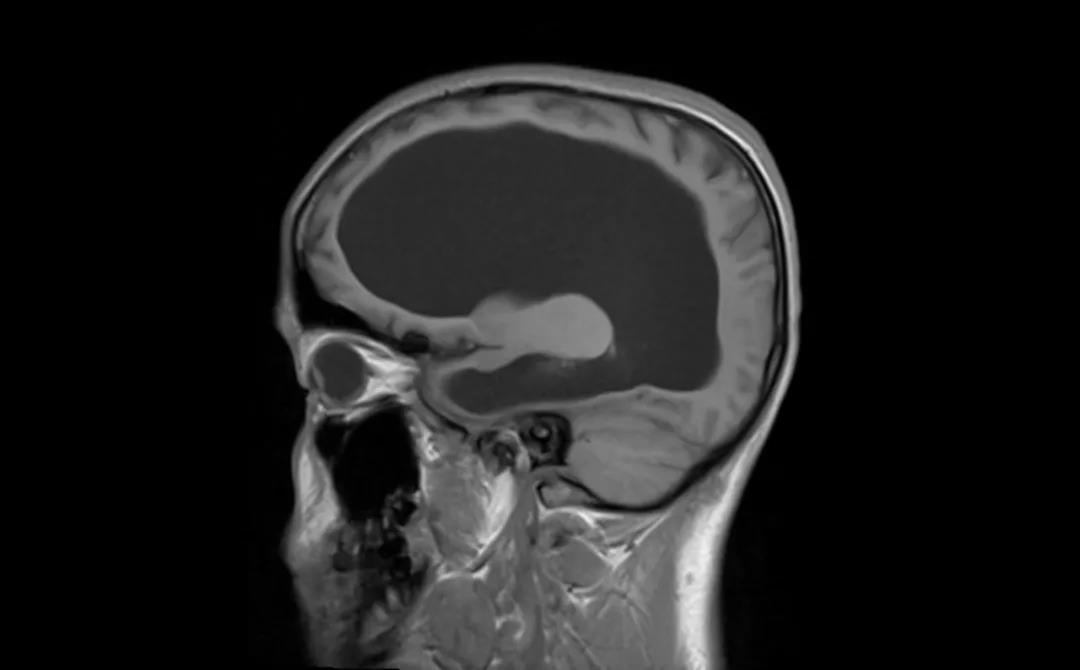

患者术前 CT

脑积水积的不是水,而是脑脊液过多,是由于颅脑疾患使得脑脊液分泌过多或(和)循环、吸收障碍而致颅内脑脊液量增加,脑室系统扩大或(和)蛛网膜下腔扩大的一种病症。